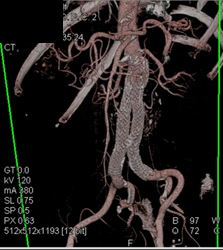

Renal Artery Aneurysm in Multiple Views